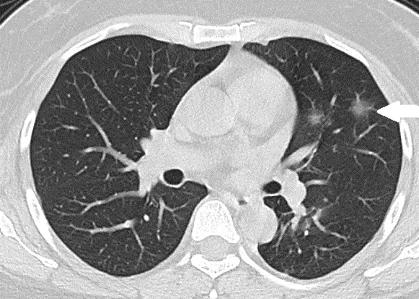

现在还处于传染病暴发前期,需要密切观察的阶段,SARS死亡率在10%左右,目前新型冠状病毒致死率没那么高。

但可能跟救治手段也有关系,现在救治手段比SARS时高。